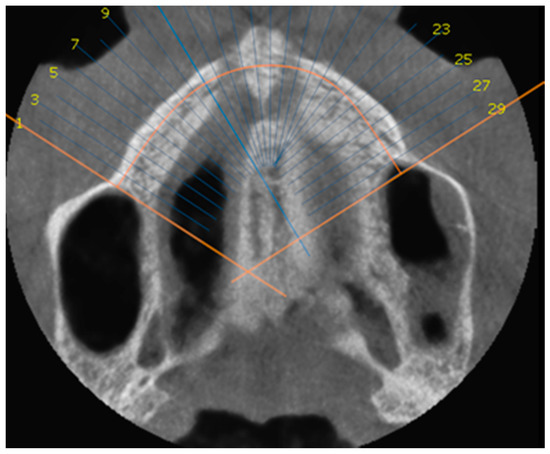

- MARPE associated with cortico-puncture therapy efficiently split the midpalatal suture in adults. The mean split at the anterior nasal spine (ANS) and posterior nasal spine (PNS) was 3.76 and 3.12 mm, respectively. The magnitude of the split at the PNS was smaller than at the ANS (by approximately 85% of the distance), showing that the opening of the midpalatal suture was almost parallel in the anteroposterior direction.

- MARPE therapy associated with cortico-puncture therapy had a positive outcome on midpalatal suture opening and maxillary advancement, but a medium molar inclination of 2.005° was also observed, suggesting that tooth movement cannot be avoided because of the anchorage of the MARPE device at the molar level.